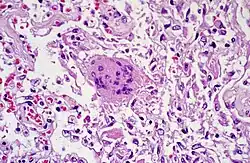

- TOUTON-Riesenzelle - Schaumzellen, bei denen um eine kleine schaumfreie Insel mehrere Kerne ringförmig angeordnet sind, Vorkommen z.B. bei juveniler Xanthogranulomatose, siehe Abb.

- Fremdkörper-Riesenzellen - Typisch in Fremdkörpergranulomen, die Zellkerne sind in einem Haufen zusammengelagert

- LANGHANS-Riesenzellen - In Tuberkulosegranulomen, die Kerne sind hufeisenförmig angeordnet

- ANITSCHKOW-Riesenzellen - Bei rheumatischer Myokarditis